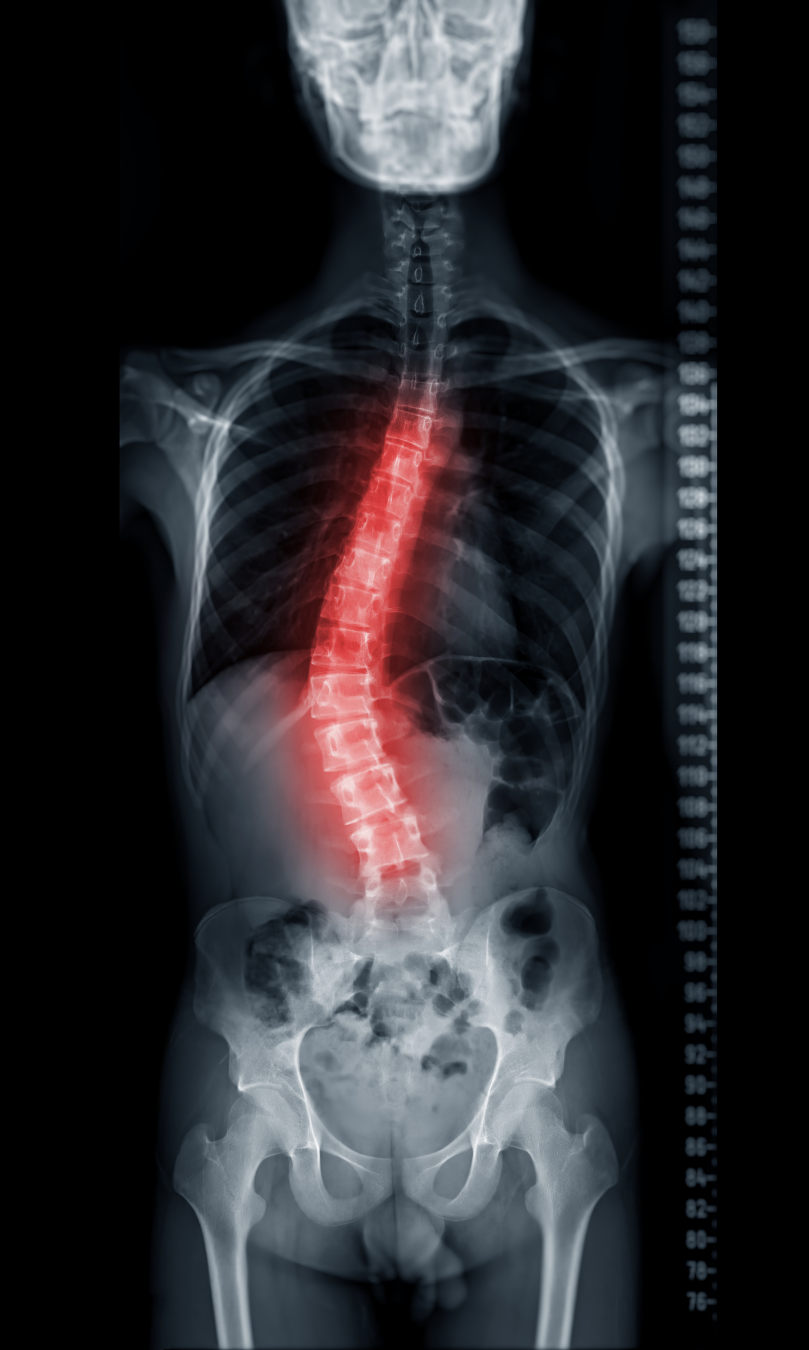

Adolescent Idiopathic Scoliosis (AIS) is the most common type of scoliosis seen during childhood and adolescence, typically developing during the growth years. It most often appears between the ages of 10 and 18, coinciding with periods of rapid growth (Shannon et al., 2021).

AIS affects approximately 2–4% of adolescents worldwide, making it far more common than many families realise (Ren et al., 2025). While many cases remain mild, some spinal curves can progress during growth spurts, which is why early identification and regular monitoring are so important.

AIS is characterised by a sideways curvature of the spine that appears without a known cause. While the exact reason AIS develops is still unclear, research shows that curve progression is closely linked to growth velocity. This means changes can happen relatively quickly during puberty and growth spurts (Ren et al., 2025).

X-rays are only recommended when clinically indicated and are typically used to monitor curve progression rather than as a routine screening tool (Wong et al., 2025; Ren et al., 2025).